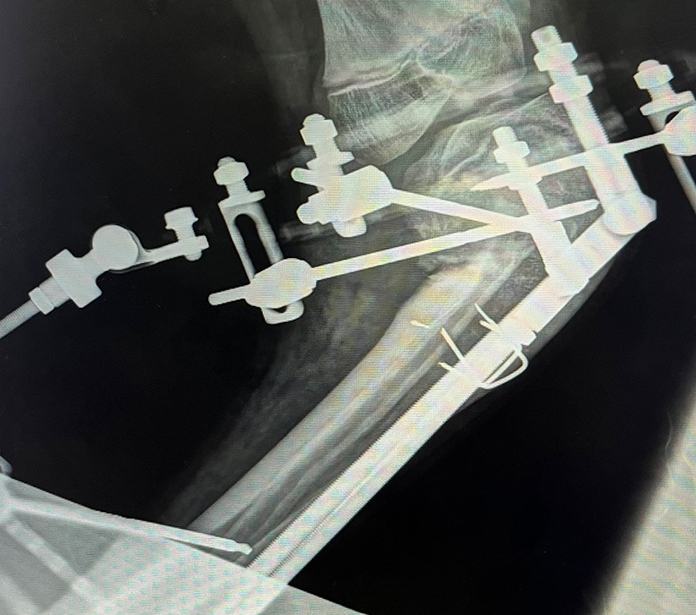

Figure 5. Post-operative AP radiograph after tibial osteotomy

Courtesy of Douglas W. Lundy, MD, MBA, FAAOS

Figure 6. AP radiograph demonstrating progressive correction of tibial deformity

Images Courtesy of Douglas W. Lundy, MD, MBA, FAAOS